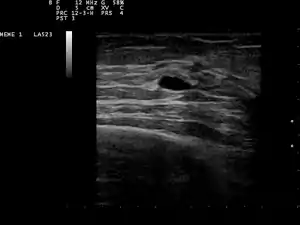

![]() мала кіста молочної залози на узі мала кіста молочної залози на узі | |

Кістозний характер грудної грудочки може бути підтверджений ультразвуковим дослідженням, аспірацією[6] (забір вмісту голкою) або мамографією. Ультразвукове дослідження також може показати, чи містить кіста тверді вузлики, оскільки це може бути ознакою ракового ураження. Дослідження цитопатологом рідини з кісти, також може допомогти в діагностиці.

Пацієнтам, у яких підозрюють кісту молочної залози, зазвичай призначають діагностичну мамографію, хоча вони і не підозрюються на рак, оскільки цей тип мамографії забезпечує лікареві можливість одночасно робити УЗД молочної залози. УЗД молочної залози вважається найкращим варіантом при діагностиці кісти молочної залози, оскільки вона точна на 95 % — 100 %, вона забезпечує чітке зображення кісти (проста або складна), а також може відрізняти тверді грудочки в грудях і кісти, заповнені рідиною, чого мамограма не може зробити.[7]